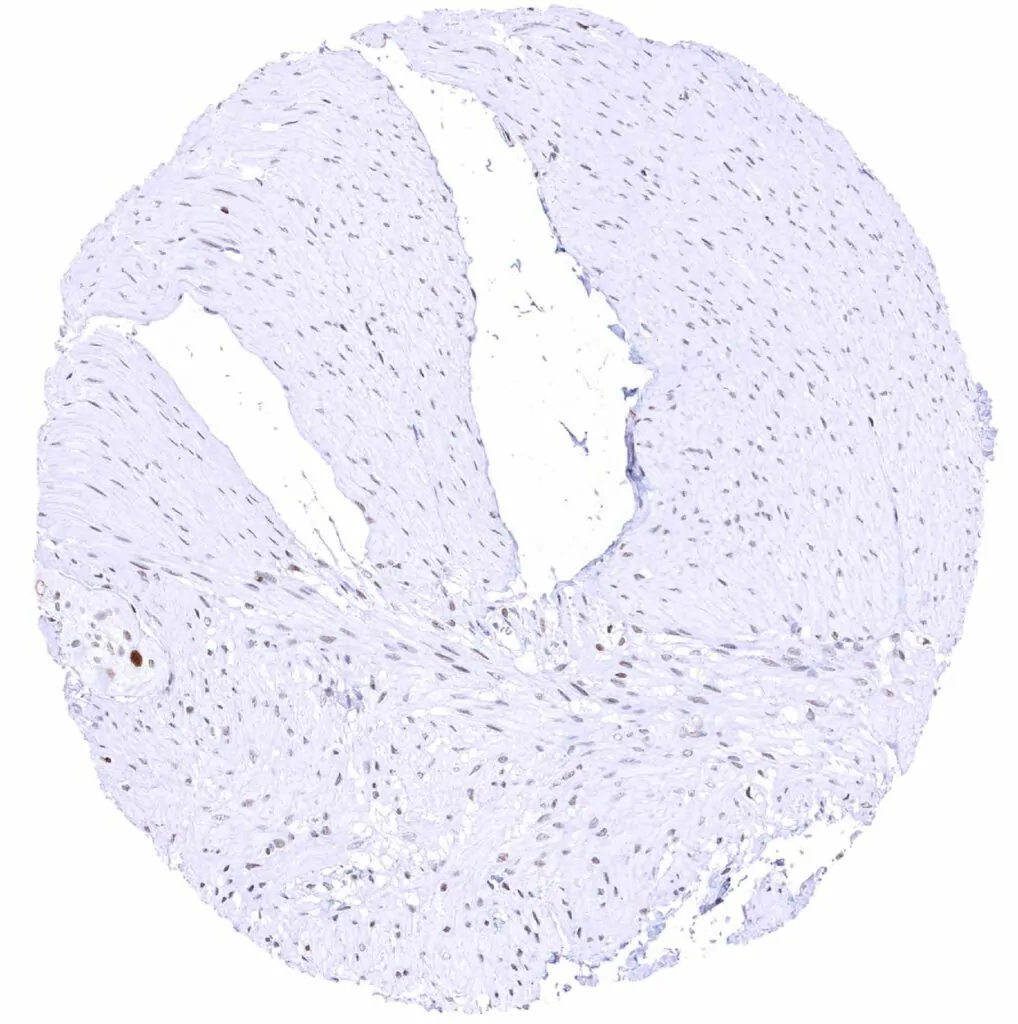

Aorta, media – Moderate TLE1 positivity of a subset of spindle cells in the media